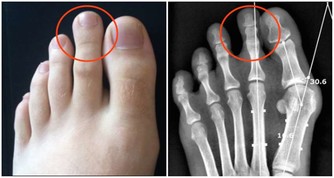

徵兆五:腎臟問題

腎功能不全,會引起腎的病變。腎的病變會讓糖尿病患者腎臟出現一定的不良反應。